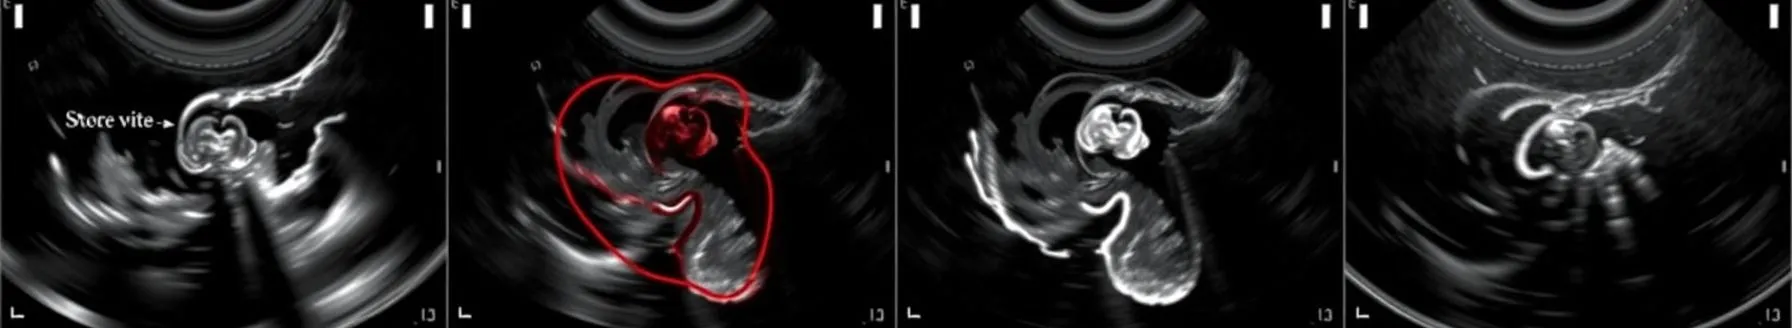

Echocardiography in Heart Failure with Reduced Ejection Fraction

Non-invasive imaging, particularly echocardiography, plays a central role in the evaluation for heart failure with preserved ejection fraction (HFpEF). Echocardiography helps to rule in HFpEF among patients with unexplained dyspnea when the diagnosis is uncertain. In established HFpEF,...

- Heart failure is a clinical syndrome characterized by symptoms and/or signs resulting from structural or functional cardiac abnormalities, corroborated by elevated natriuretic peptide levels and/or objective evidence of pulmonary or systemic congestion. It is classified based on ejection fraction (EF): reduced (≤40%), mildly reduced (41-49%), and preserved (≥50%).